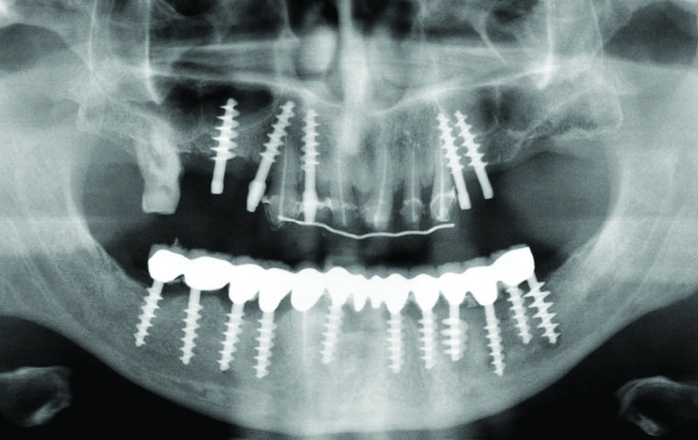

She is a graduate of Broome Community College, NY with 27 years of clinical practice experience. She began her dental hygiene career in the Center for Osseointegration in Washington DC, which specialized in dental implants and prosthetics. Her professional speaking career paralleled with her clinical career, consulting for an international dental implant company. Lisa is an active member of the ICOI and ADIA, two organizations dedicated to education pertaining to dental implants, as well as a member of the Speakers Consortium for Straumann, and an active, committed board member of the National Speakers Association.

Dental Implants: Successful Assessment and Maintenance for Lifelong Oral Health

Dental implants have become a standard of care. Are you prepared? Long term success is dependent on comprehensive clinical evaluation, effective communication and appropriate clinical / patient therapies. This course is designed for …